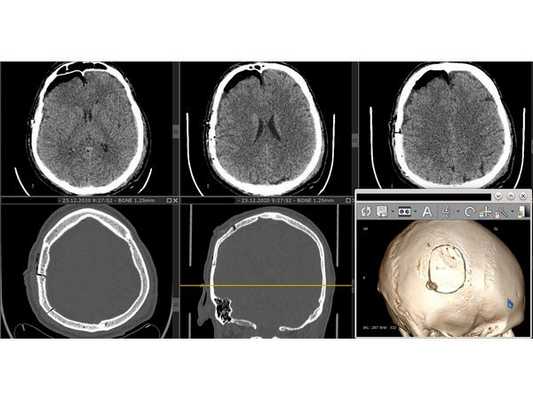

- Выполнен дугообразный разрез мягких тканей с захватом имеющейся раны.

- Скелетирована кость (надкостница отделена от кости). Гемостаз (остановка кровотечения) по ходу доступа. Визуализирован импрессионный перелом правой теменной кости.

- Краниотомом наложено фрезевое отверстие ниже вдавленного перелома и выпилен костный лоскут 5,0 х 6,0 см с захватом имеющегося импрессионного перелома. Костный лоскут временно удалён.

- Выполнена репозиция вдавленных фрагментов.

- Твёрдая мозговая оболочка (ТМО) вскрыта подковообразным разрезом. Путём аспирации (всасывания) и отмывания физиологическим раствором удалена пластинчатая субдуральная гематома малого объёма. ТМО ушита непрерывным швом с одновременным подшиванием по периметру трепанационного окна.

- Костный лоскут многократно обработан 3 % раствором перекиси водорода и уложен на место. Выполнен послойный шов раны. Кожные края ушиты непрерывным швом по Мультановскому.

На контрольной КТ головного мозга в послеоперационном периоде видна положительная динамика: состояние после краниотомии, репозиции вдавленных фрагментов теменной кости, удаления субдуральной гематомы, регресса дислокации срединных структур стабильное.